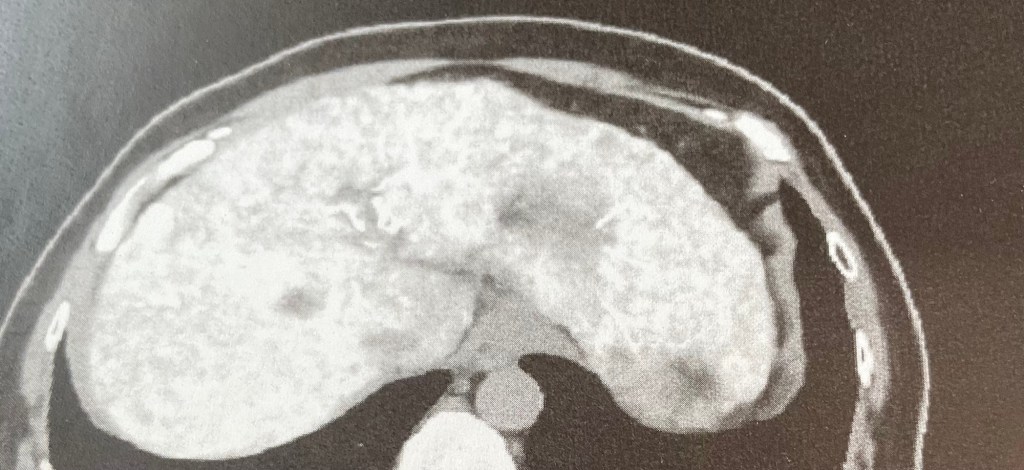

今回の手術は、カテーテルを鼠蹊部から入れて、肝臓内に抗がん剤を満遍なく散布して、腫瘍を消すというもの。

手術を受けた1月14日水曜日の夕方に、主治医さんが病室にいらして、この写真を私に見せて、「ねー綺麗に染め上がってるでしょー」と自慢げにおっしゃいました。

……………染め上がってるってさあ…‥

藍染めか。いや抗がん剤染めだぞ。